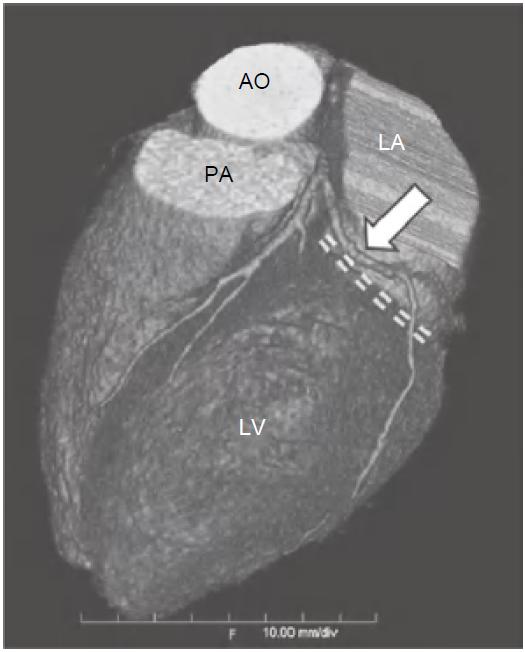

冠状动脉左主干(LMS)通常起源于左冠窦,位置低于RCA开口平面。通常在左心耳及肺动脉主干之间走行约1~2cm后分为LAD及左旋支(LCX),LAD在前室间沟内向下延伸至心尖(图13-1),LCX在左房室间沟(LAVG)内向后走行(图13-2)。

图13-1 左前降支(箭)起自左主干分叉处,并在前室间沟(虚线)内走行,为前壁、心尖部及大部分室间隔供血

AO.主动脉;PA.肺动脉;RV.右心室;LV.左心室